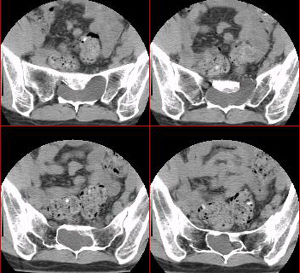

CT檢查

可清楚顯示骨質破壞和占位病變,尤其對骶骨顯示清晰。

CT及MRI特點骶管囊腫因其位置的特殊性,臨床表現又與其他椎管內疾病相似而未引起人們的重視,CT掃描腰椎間盤不容易注意骶管情況而漏掃,除非骶管囊腫引起明顯骶管骨質吸收,CT的密度解析度最高,對囊腫周圍骨質結構的改變顯示最佳,評價囊腫對椎管骨壁的壓迫性骨質吸收優於MR,若結合增強掃描,亦能大致確定囊腫的性質;但是由於受骨偽影及解析度的影響,腫瘤與周圍組織的關係在CT上顯示欠清晰,由於M R I對水的敏感度很高,囊性病灶的診斷中,C T不及MRI;MRI因其無創,軟組織分辨力高,多方位成像又無骨偽影,能較好顯示囊腫大小、數目、分布、內部結構其與周圍組織的關係,其MRI表現:

骶管囊腫(1)囊腫位於骶管內,呈卵圓形,串珠狀及不規則形,可以單發或多發。(2)囊腫境界清楚,囊壁菲薄,信號與腦脊液相似,T1W I呈均勻一致的低信號,T2WI呈均勻的高信號,增強掃描囊壁及囊液無強化。(3)囊腫主要位於骶1-3椎平面骶管內。